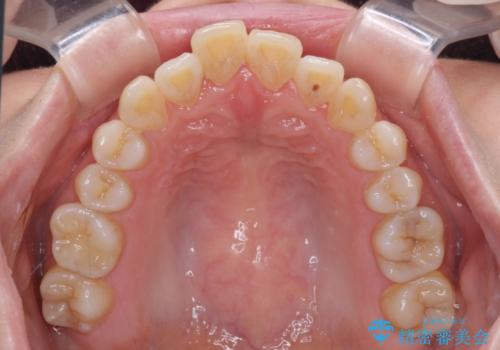

- 口元の突出感と口の閉じにくさを気にして来院された患者様です。

上下左右第一小臼歯4本を抜歯し、ワイヤー装置にて口元を引っ込めるよう矯正治療を行うこととしました。

2年~2年半が治療期間の目安でしたが、順調に治療が進み、1年9か月で満足のいく歯列となりました。